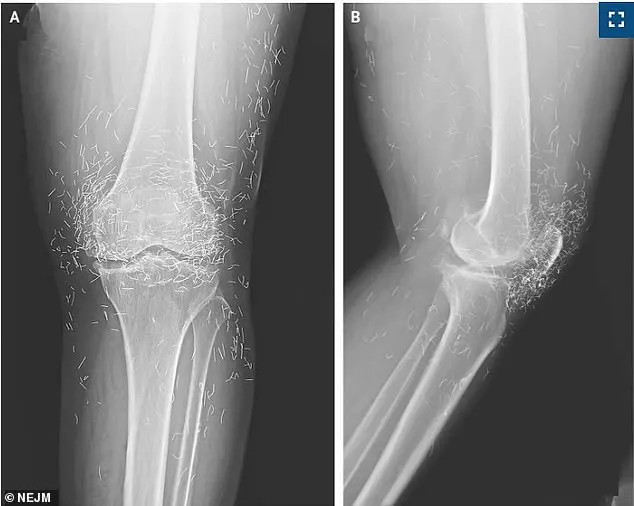

The patient, who had been undergoing gold thread acupuncture—a practice involving the insertion of sterile gold threads into the skin—was shocked to discover during an X-ray that hundreds of these threads had been left in her knees.

However, the presence of these threads in her knee, revealed by the X-ray, complicated her doctors’ ability to assess the true state of her joint damage.

The woman’s case, detailed in the New England Journal of Medicine, has drawn attention from the medical community.

Doctors treating her noted that the gold threads obscured critical anatomical details on scans, making it harder to diagnose her condition accurately.